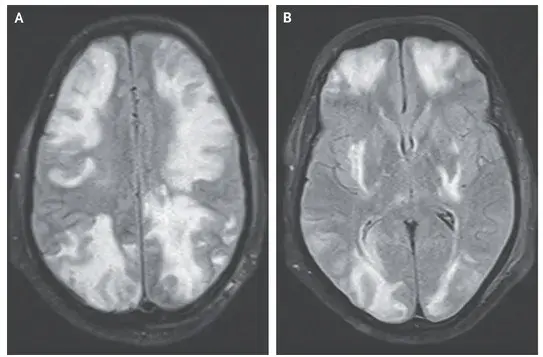

Caso clínico publicado no NEJM: Um homem de 35 anos com nefropatia por IgA procurou pronto-socorro com quadro de confusão mental, visão embaçada e convulsão há 01 dia. Duas semanas antes da apresentação ele começou a tomar ciclosporina para tratamento de nefropatia por IgA. Sua PA era de 160/80 mm Hg. Ao exame físico paciente